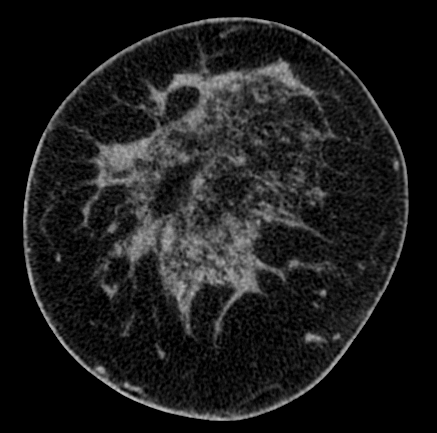

Refer to caption

(a)

(b)

(c)

Figure 3: (a) Coronal slice of a breast CT image, (b) the same image classified into skin (white), adipose (dark gray) and fibroglandular (light gray) tissue voxels, and (c) the classified deformed image with the technique described in Section 3.2.

Using this method, of which an example is given in Figure 3, we obtained a total of 28891 deformed BCT slices extracted from 91 different patient breasts. Similar to the virtual phantoms the resulting images have dimensions of 1000×30010003001000\times 300 pixels and a resolution of 200 µmtimes200micrometer200\text{\,}\mathrm{\SIUnitSymbolMicro m}. Given that the number of deformed BCT slices was substantially lower than that of virtual phantom slices, we pre-trained the model with the latter, and then fine-tuned the model using the BCT slices from 46 patient BCT images. The other 45 patient BCT image phantoms were used for testing the reconstruction performance of the model and the accuracy of density and dosimetry estimates. Each patient breast was either completely included or excluded when selecting slices for fine-tuning and testing the model in order to prevent data contamination and bias.